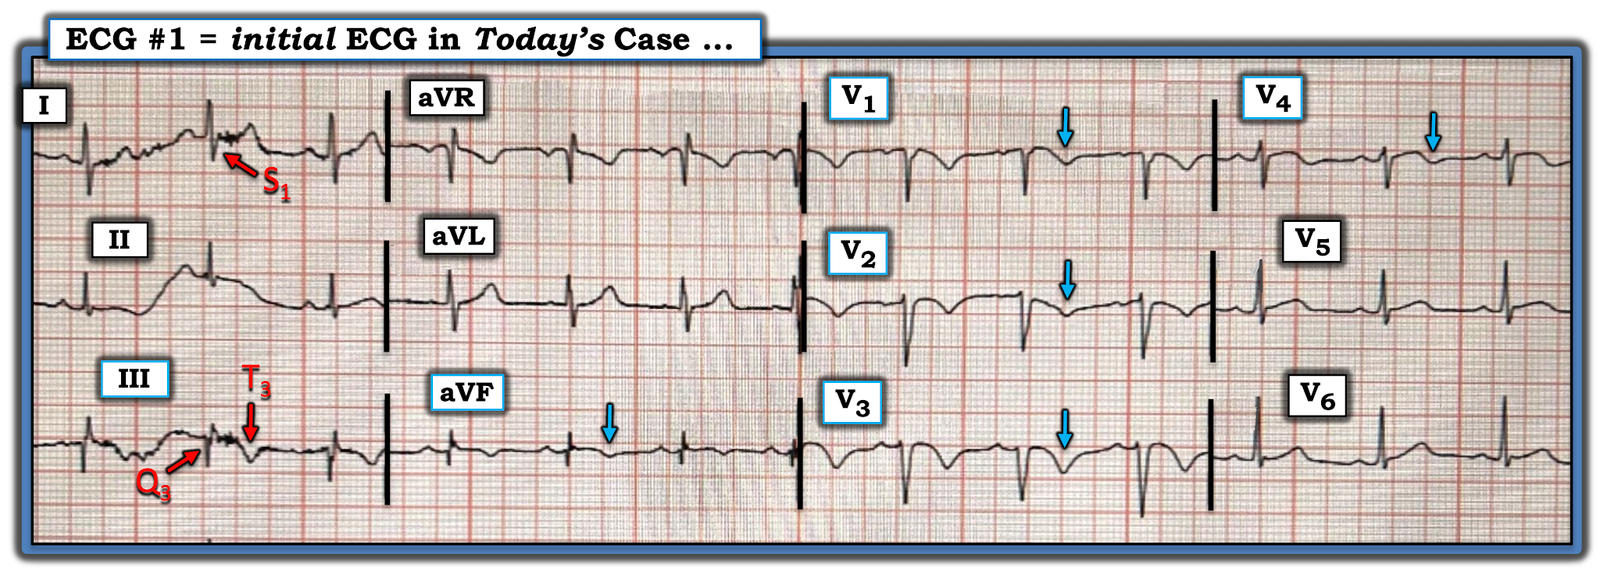

We’ve reviewed the ECG clues to acute PE in those more than 20 links that Dr. Meyers’ lists above. I found today’s initial ECG interesting — in that most of the time, the ECG diagnosis of acute PE is highlighted by more than just a couple of the ECG Findings that I list below in Figure-2.

- For example, in today’s initial ECG (that I’ve reproduced and labeled in Figure-1) — there is no sinus tachycardia — and no right axis, RAA, incomplete or complete RBBB, tall R in lead V1, persistent precordial S waves, ST elevation in lead aVR or AFib.

That said — the following are present in today’s case:

- An S1Q3T3.

- Deep symmetric T wave inversion in the anterior chest leads (BLUE arrows in Figure-1) — that occurs in association with T wave inversion suggesting RV “strain” is present not only in the anterior chest leads, but also in inferior leads III and aVF.

PEARL (as per Drs. Meyers and Smith): When there is T wave inversion in the chest leads — IF there is T wave inversion in both lead V1 and lead III ==> Think acute PE (and not ACS! ).

- By itself — the S1Q3T3 sign seen in Figure-1 would not be specific for acute PE (ie, I have seen this sign in healthy individuals with no acute pulmonary pathology). However, in the presence of a suggestive history and the extensive T wave inversion seen in today’s case — the S1Q3T3 strongly supports the diagnosis of acute PE.

- T wave inversion as diffuse as is seen in Figure-1 — most often suggests a sizeable PE (which makes it all the more surprising that there is no tachycardia and a lack of more of those ECG findings that are listed in Figure-2).

- Finally — the Q in lead III — the ST coving with slight ST elevation + T wave inversion in leads III and aVF — and the ST segment straightening in lead aVL — might lead one to misinterpret today’s ECG as indicative of ACS. IF tempted to do so — it is worth rereading the above PEARL!

Figure-1: I’ve labeled the initial ECG in today’s case.